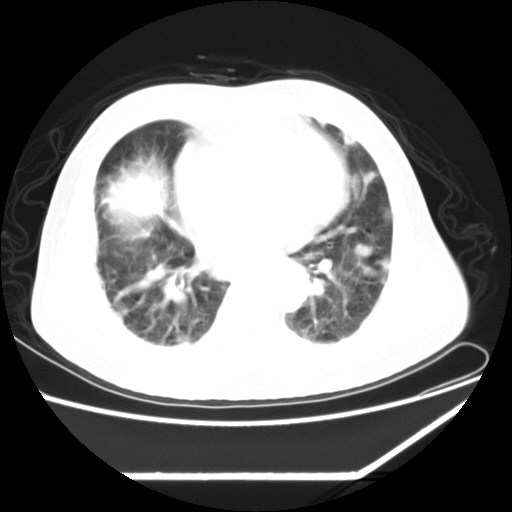

男,57,畏寒,发热

两肺野多发大小不一高密度灶,纵膈内见肿大淋巴结,要考虑转移瘤可能。双侧胸腔少量积液。

双肺多发结节样病灶,部分内见透光区,纵隔内见淋巴结肿大。结核临床如有畏寒,高热,白细胞增高首先考虑迁徙性肺脓肿(多是金黄色葡萄球菌感染)。

注意除外转移瘤。

1)考虑两肺感染性病变(金黄色葡萄球菌肺炎?);建议抗炎治疗后复查排除其他。2)双侧少量胸腔积液。